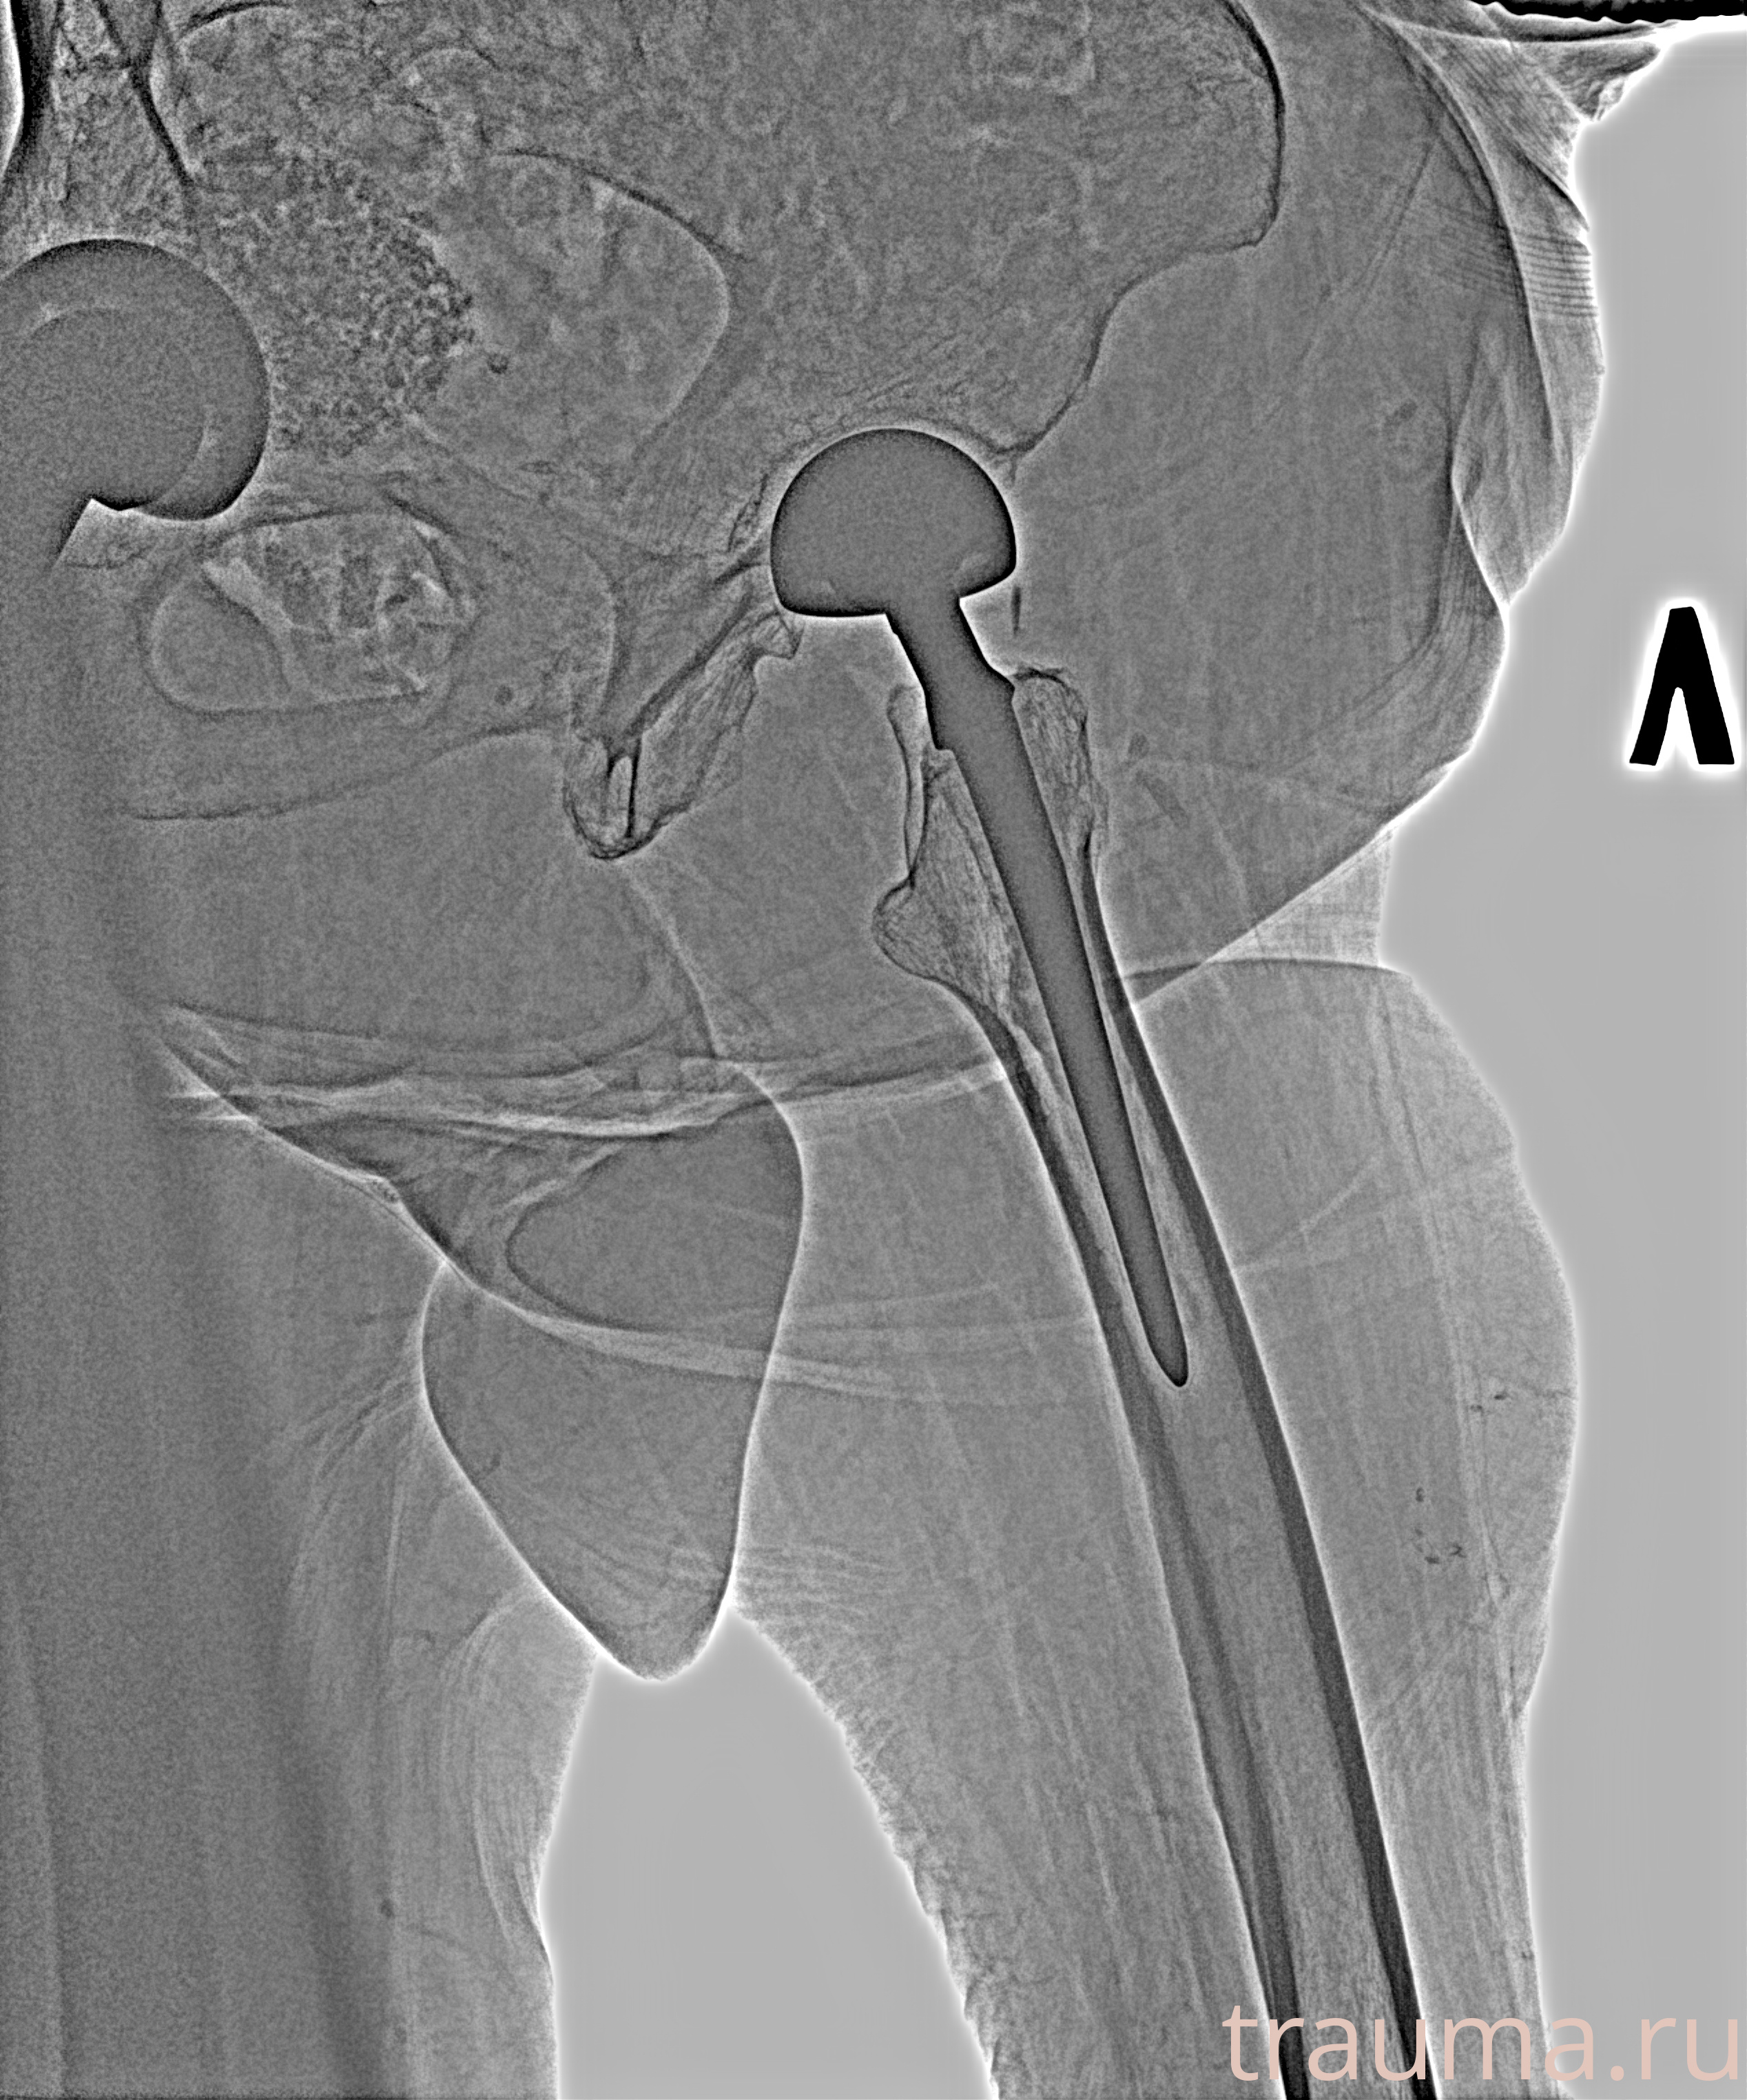

Рентген на дому: по вашему адресу приезжает врач-рентгенолог, травматолог-ортопед с мобильным рентгеновским аппаратом, проводит диагностику травмы или заболевания, делает необходимые рентгенограммы, дает рекомендации по дальнейшему лечению. Получить качественные снимки в домашних условиях возможно благодаря уникальной методике, разработанной МосРентген Центром для института  Склифосовского